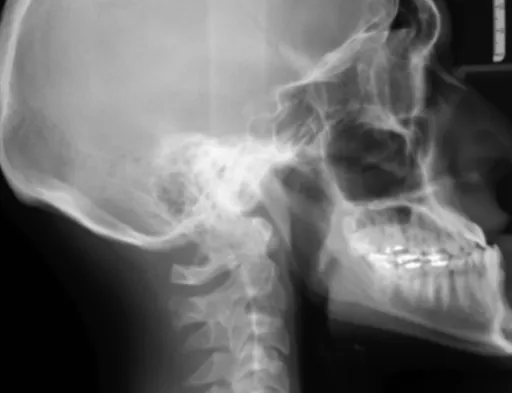

류마티스 관절염 초기 증상 을 의심하고 병원을 찾으면, 의사 선생님께서는 여러 가지 방법으로 진단을 내리게 돼요. 먼저, 환자의 증상과 병력을 꼼꼼하게 듣고, 신체검진을 통해 관절의 붓기, 열감, 운동 범위 등을 확인하게 됩니다. 그리고 혈액검사를 통해 류마티스 인자(RF)나 항CCP 항체 같은 특정 항체의 수치를 확인하고, 염증 수치(ESR, CRP)를 통해 염증의 정도를 파악하게 돼요. 또한, X-ray, 초음파, MRI 등의 영상 검사를 통해 관절의 손상 정도나 염증 부위를 확인하면서 정확한 진단을 내리게 된답니다. 이런 종합적인 검사를 통해 류마티스 관절염 을 조기에 진단하고 적절한 치료 계획을 세우는 것이 중요해요.